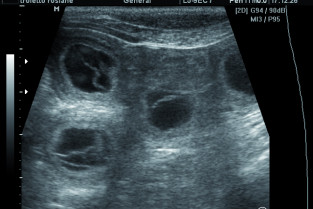

Emmanuel Topie (Dipl. ECAR, GERES), fort de son expérience universitaire et libérale, viendra vous présenter les dernières recommandations en matière de reproduction. Il abordera le suivi de la gestation chez la chienne et la chatte, depuis la confirmation de la gestation à la mise bas. La prévision, et l'anticipation de la mise bas n'auront plus de secret pour vous à l'issue de son exposé.

• connaître les méthodes de diagnostic de gestation ainsi que leurs intérêts et limites ;

• réaliser un suivi de gestation et une prédiction de mise bas ;

• anticiper les gestations à risque et proposer des méthodes préventives ;

La gestation : confirmation, suivi, prédiction de la mise bas et anticipation des risques